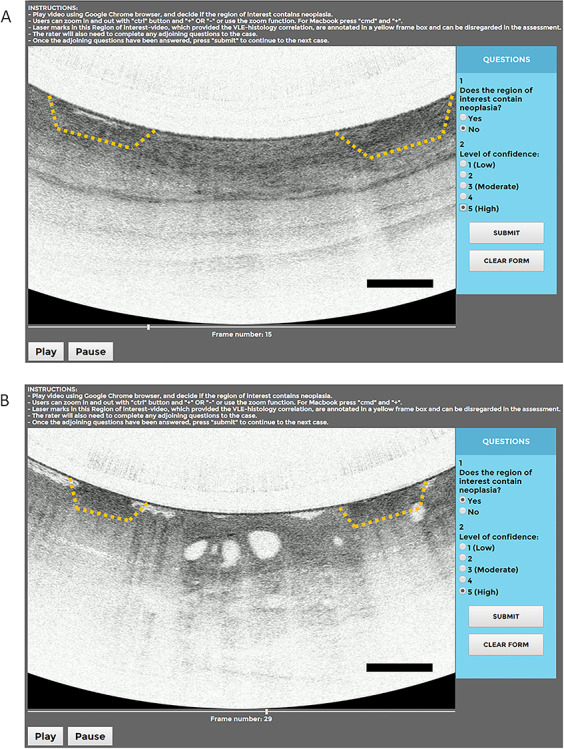

Fig. 3.

(A) Web-based module showing a nondysplastic Barrett’s volumetric laser endomicroscopy (VLE) region of interest. Corresponding questions, including levels of confidence, were scored for each region of interest. In the VLE image, the laser marks (yellow box) are visible as small areas of high surface signal intensity. (B) Web-based module showing a neoplastic Barrett’s VLE region of interest. Corresponding questions, including levels of confidence, were scored for each region of interest. In the VLE image, the laser marks (yellow box) are visible as small areas of high surface signal intensity.